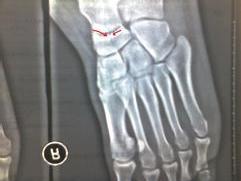

凡疑為骨折者應常規進行X線拍片檢查,可顯臨床上難以發現的不完全性骨折、深部的骨折、關節內骨折和小的撕脫性骨折等,即使臨床上已表現為明顯骨折者,X線拍片檢查也是必要的,可以幫助了解骨折的類型和具體情況,對治療具有指導意義。

3、影像學檢查 :一般無須行CT,MRI等檢查,而僅需常規X線片即可明確診斷,有時尚需行X線斜位攝片。

舟骨結節撕脫骨折者應與舟副骨相鑑別,後者屬先天發育性,邊緣光滑整齊,類似關節。